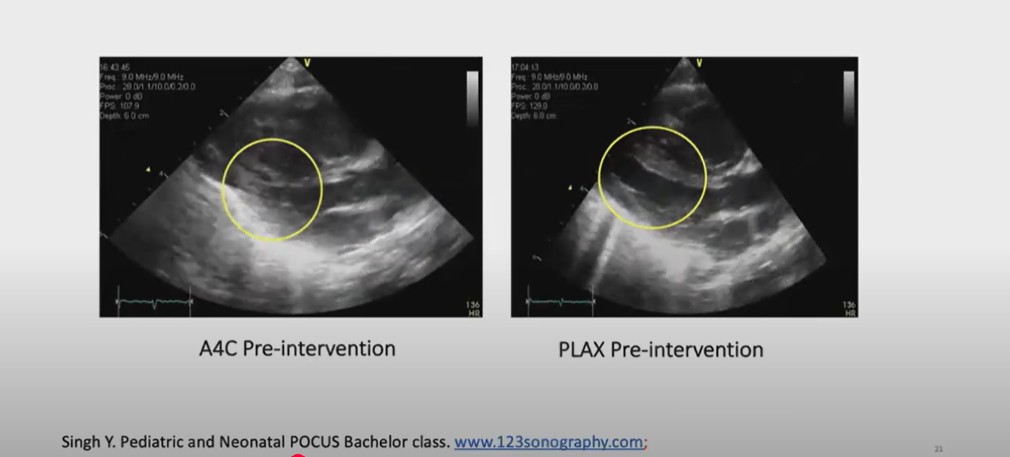

I’ll present only the

pocus part today and in this case how that can be helpful even let’s look on these two

views on this side you can see the epical four chamber V and you can see the rights of the heart is much bigger

right ventricle is almost double the size maybe bigger than the right left ventricle see with the right atrium is

much bigger in the par long AIS V right

ventrical is is big is Hy trage in vental septum is here and you can see

the poster free wall which is left vental freeall here but you can see in the para

long access V the in vental septum and the poster free wall they’re touching

each other we call it a kissing sign of the left ventricle that’s a good sign of the

hypovolemia sometime with a bad like significantly hyper of left right ventricle in ventrical sep may come

towards the Left Post wall but hardly touches but here you can see it’s almost

dividing the cavity into two one towards the Apex once toward the left ventrical

outl track here just in the focus on the focus

images you can look on the multiple views maybe at least three views epical four chamber per perest long ACC View

15:2716:2716:41 [These images below are mislabeled, I think. Left image is PLAX pre-intervention. Right image is PLAX post intervention. Left image shows post free wall and septum kissing. Right image shows post intervention and the left ventricular volume has increased.]